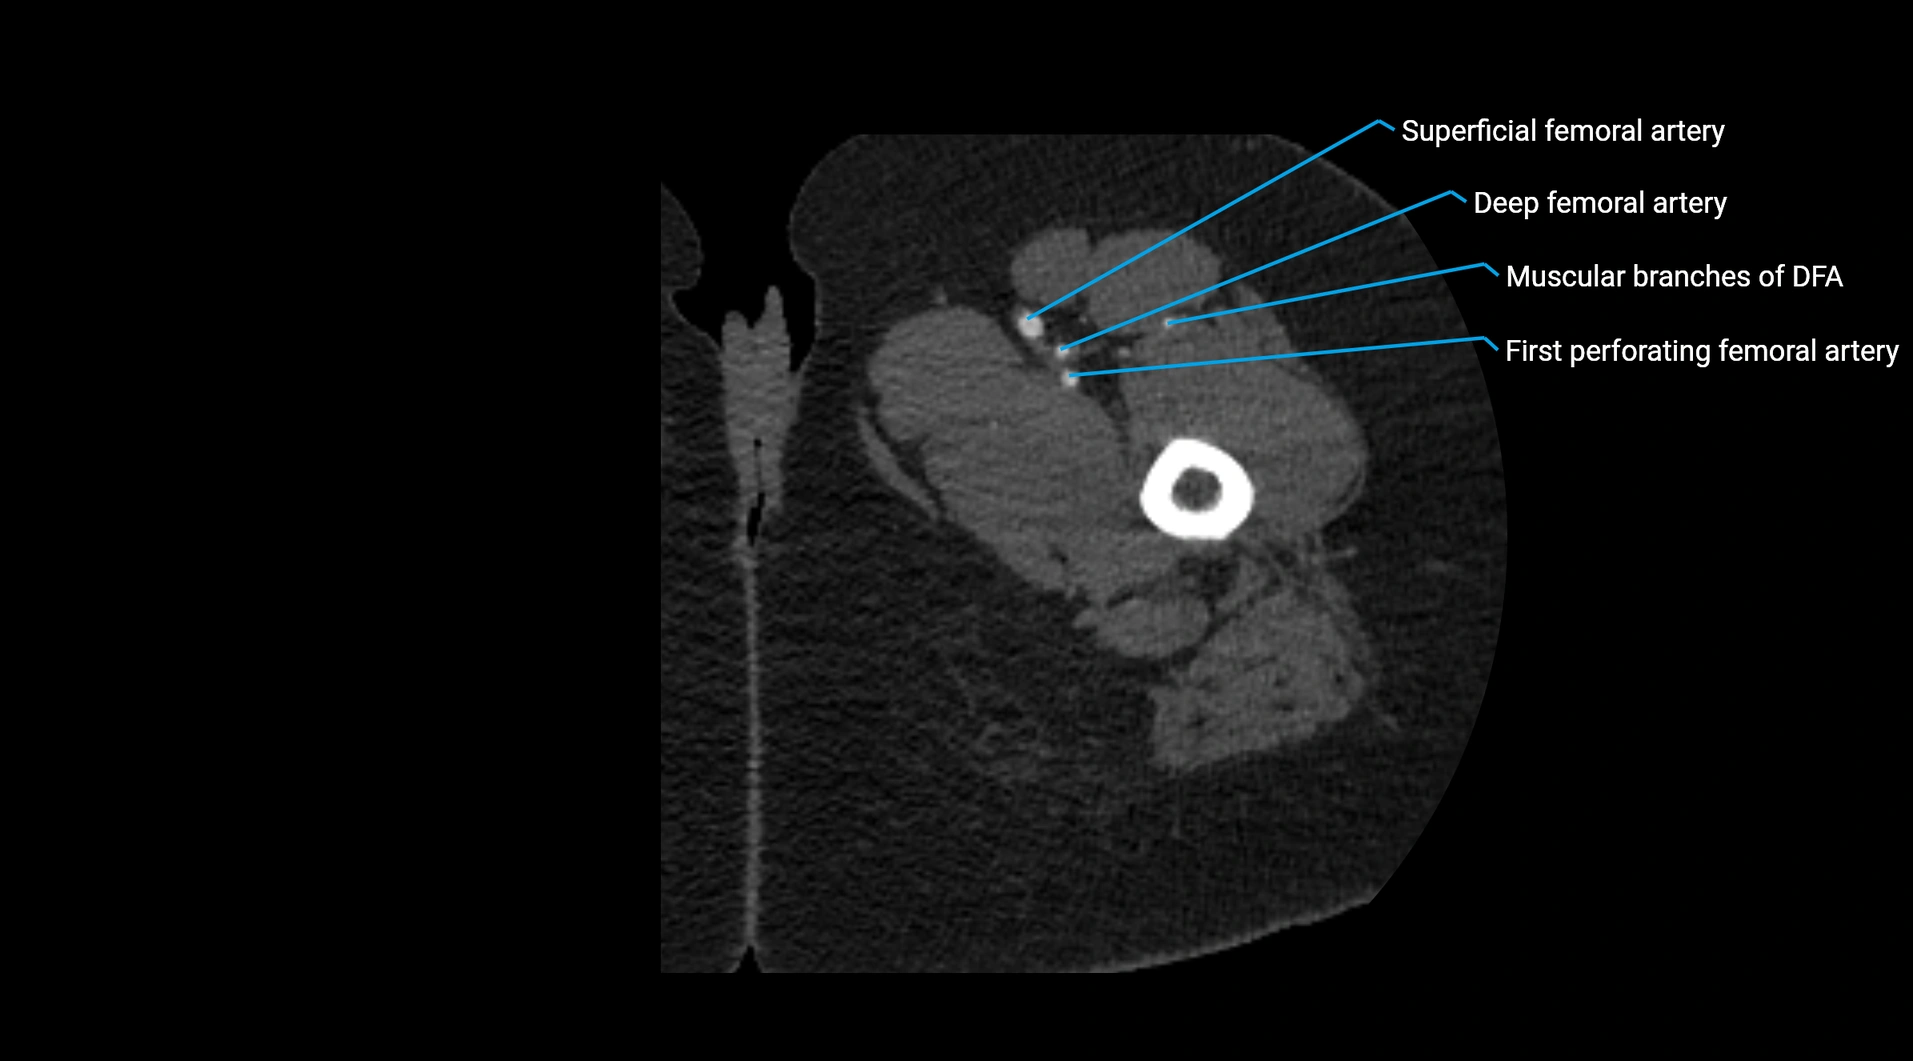

Contrast-enhanced CT (CTA):

• Gold standard for abdominal aortic imaging

• Provides excellent detail of lumen, wall, aneurysm, thrombus, and branch vessels

• Multiplanar and 3D reconstructions help in aneurysm measurement, stent graft planning, and dissection evaluation

• Detects acute rupture, traumatic injury, or occlusion with high sensitivity